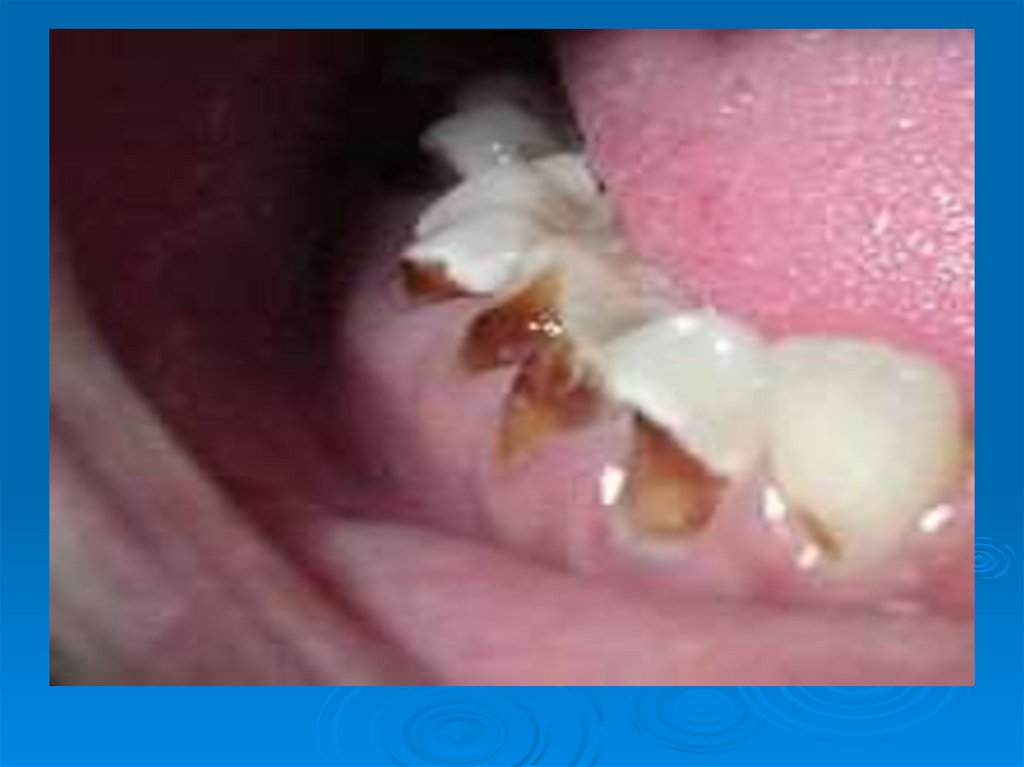

Кариес зубов – патологический процесс, проявляющийся после прорезывания зубов, при котором происходят деминерализация и

Современная концепция этиологии кариеса

6. Кариес зубов – патологический процесс, проявляющийся после прорезывания зубов, при котором происходят деминерализация и

размягчение твердых тканей зуба с

последующим образованием

дефекта в виде полости.

Кариес – это моноэтиологическое и

полифакторное заболевание